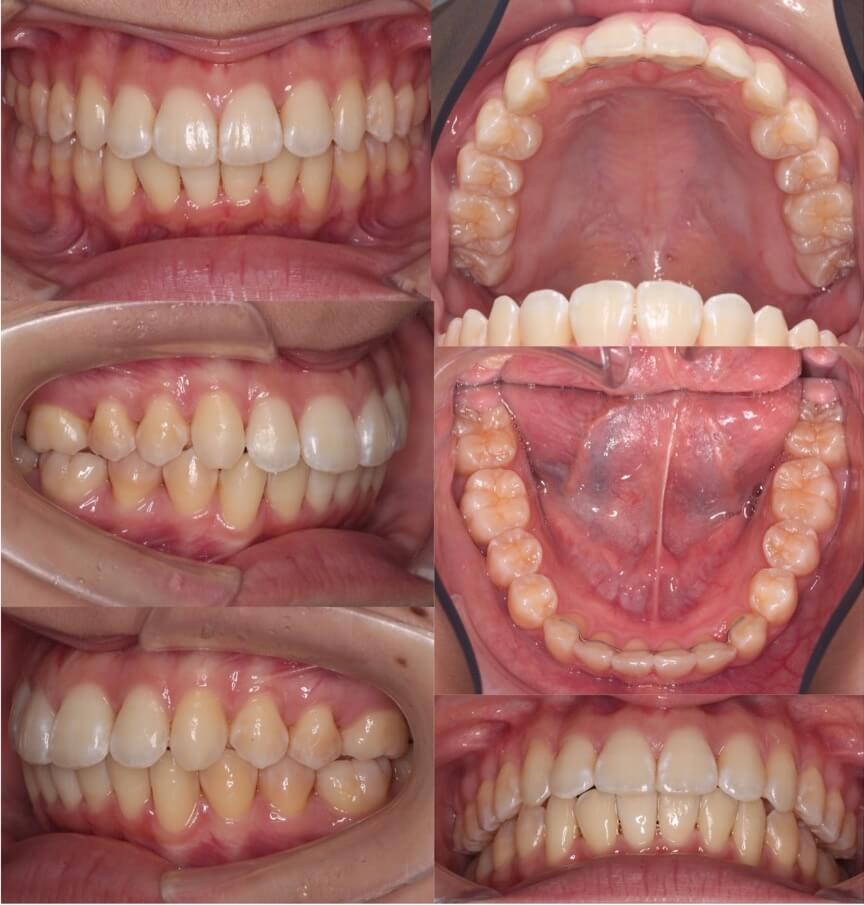

大学生女性・マウスピース型矯正装置・上抜歯

典型的な上のみの抜歯症例です。II級顎間ゴムを使用しながら、ゆっくりと前歯を後方移動させていきました。

<症例概要> 難易度★★★☆☆

主訴:出っ歯

年齢・性別:高校生女性

住まい:千葉県旭市

症状:上顎前突

治療方針:抜歯空隙閉鎖

治療装置:マウスピース型矯正装置(アライナー装置)

抜歯:上左右第一小臼歯(計2本)

治療期間:2年4か月(1週間交換)

アライナー枚数:47+37+16ステージ

リテーナー:上下フィックスタイプ+クリアタイプ

治療費用:990,000(税込)

代表的副作用:痛み・治療後の後戻り・歯根吸収・歯髄壊死・歯肉退縮

▶︎その他の副作用

【治療シミュレーション】

先に上の犬歯のみ抜歯スペースに引き、途中から残りの前歯も後ろに引きます。

※マウスピース型カスタムメイド矯正歯科装置は完成物薬機法対象外の矯正装置であり、医薬品副作用被害救済制度の対象とはならない可能性があります。